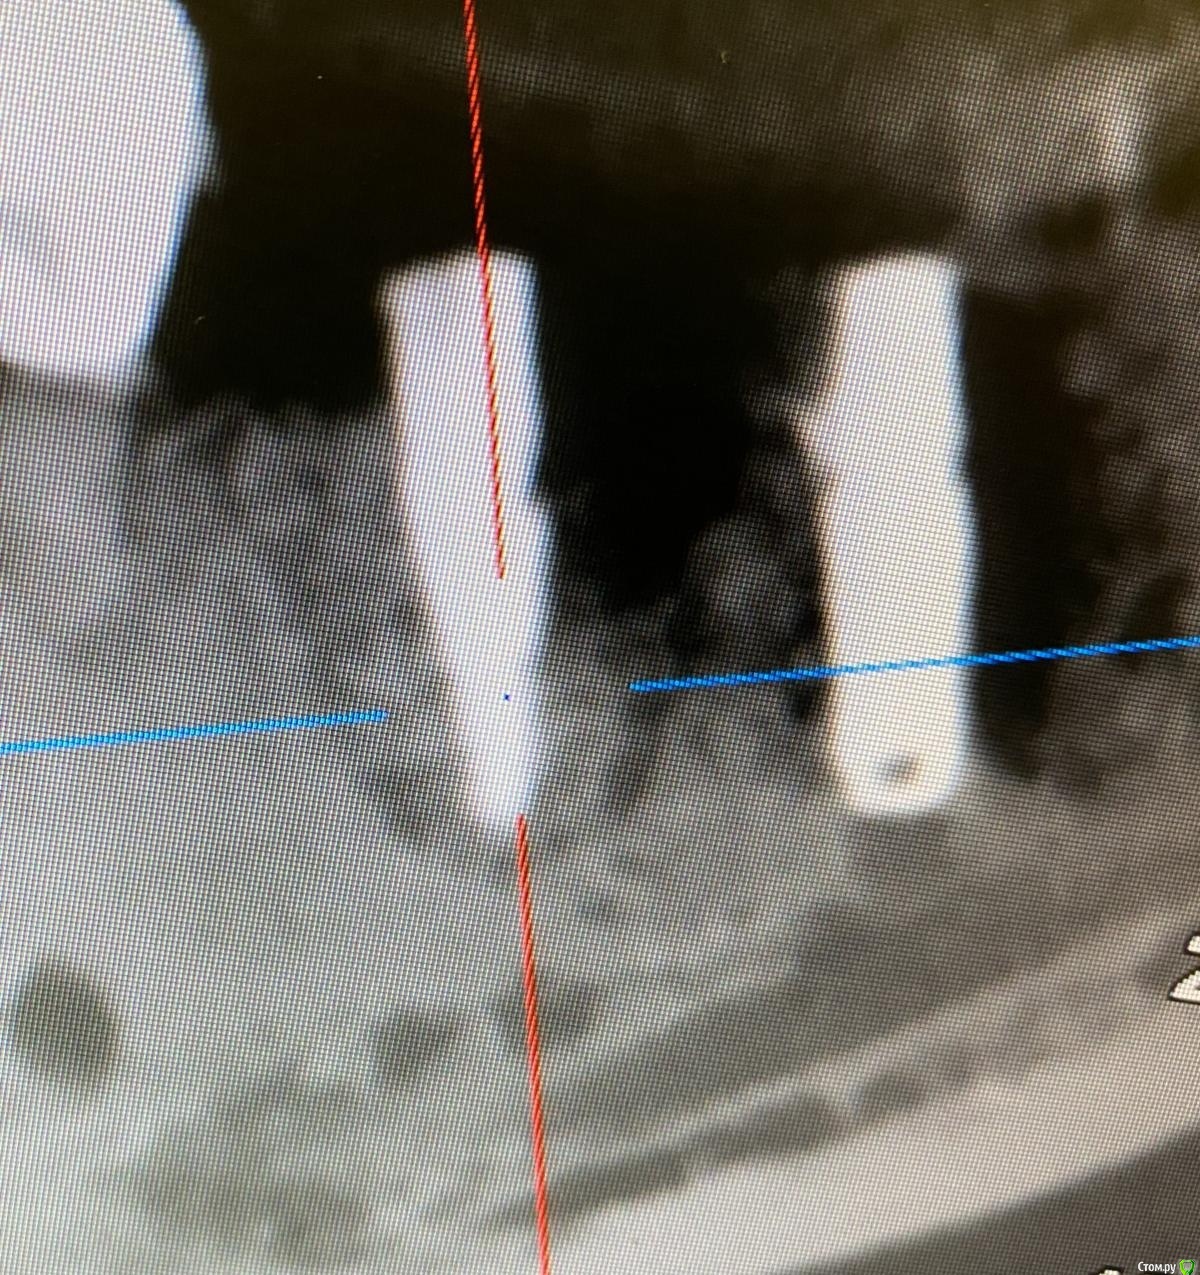

red_butler Опубликовано 15 декабря, 2020 Поделиться Опубликовано 15 декабря, 2020 сделайте прицельный снимок, похоже банальный перегрев и винт на выход 1 Ссылка на комментарий

колесников Опубликовано 15 декабря, 2020 Поделиться Опубликовано 15 декабря, 2020 Про кортикалку это я предположил. Подумал что воспроизвели так же как виртуально планировали. По снимку имплант дезинтегрирован. Я бы заменил одномоментно на другой или через консервацию,как пациент настроен. 1 Ссылка на комментарий

Bier Опубликовано 16 декабря, 2020 Поделиться Опубликовано 16 декабря, 2020 @Bier, Олег Юрьевич, скажите пожалуйста, что думаете? @колесников, ваше мнение тоже интересует. (простите не знаю как ваши ИО ) Там на лицо резорбция вокруг имплантата. Я за удаление. Ссылка на комментарий